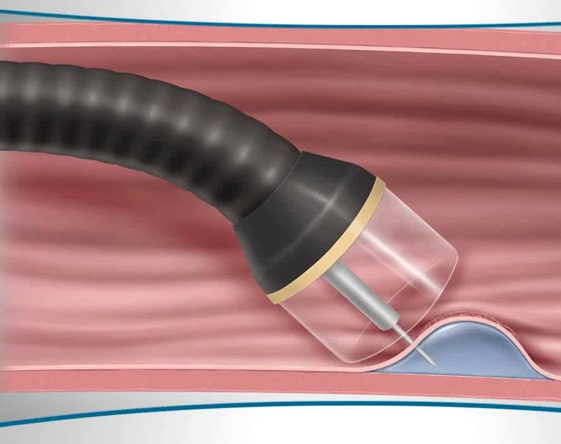

Balloon Enteroscopy

Endoscopy of the small bowel. The balloon-assisted enteroscopy is an incision-less....

I am 29 years old and I was very obese. I was unable to lose weight by dieting and because of pain in my joints, I could not exercise. Our family doctor referred me to SR Kalla hospital. I underwent the Endoscopic Balloon procedure. I have lost 17kgs in the last 4 months. Got my balloon removed today. Doctors and other staff are very nice too. Thanks a lot!